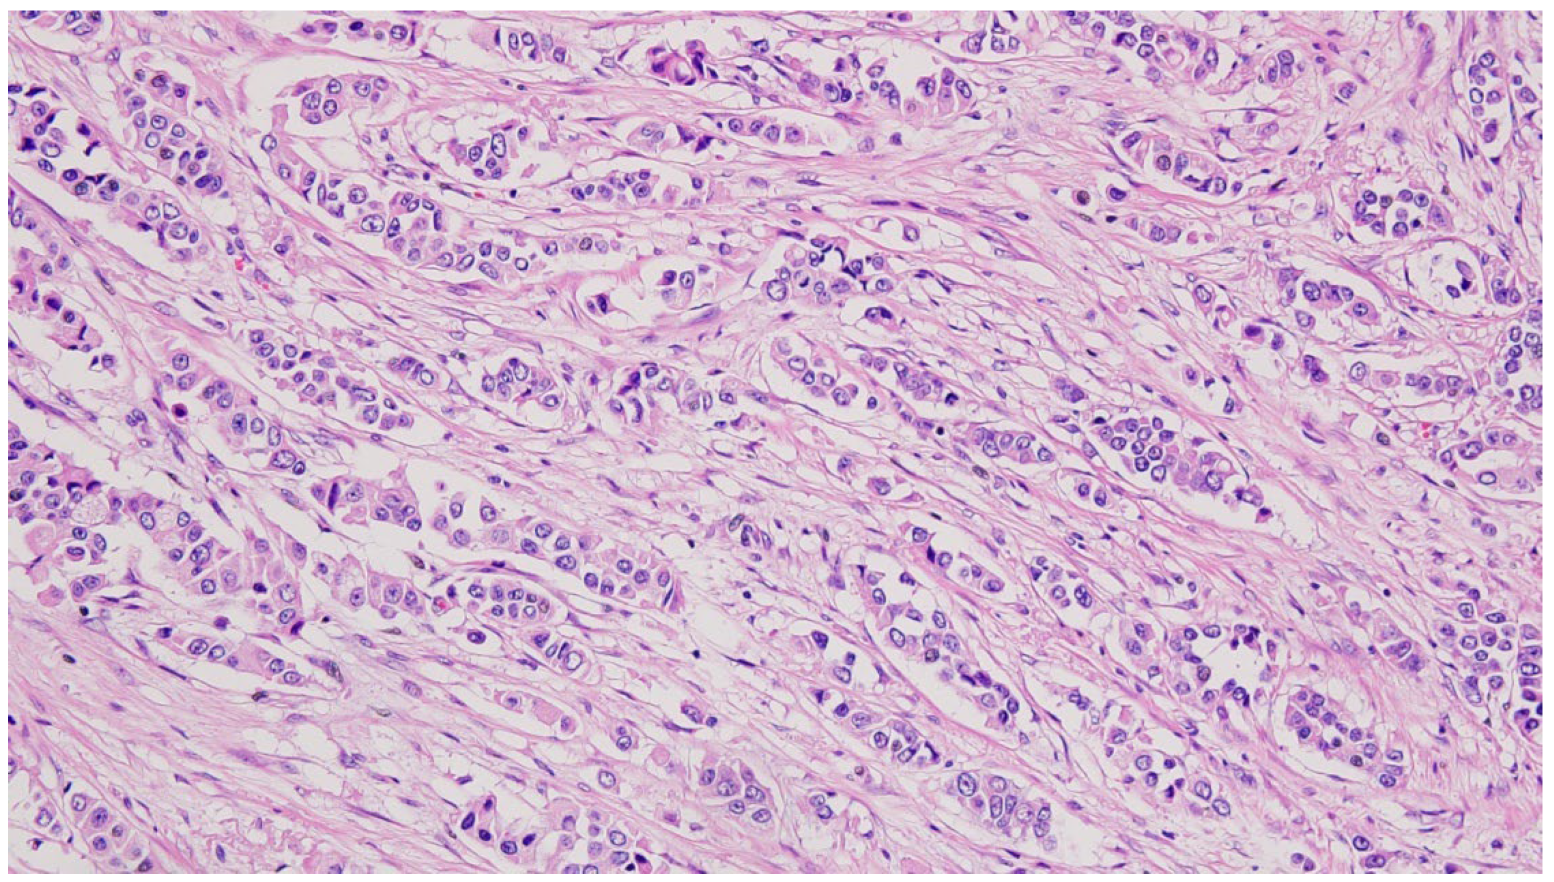

- The diagnosis of invasive ductal carcinoma and its classification as cT3N1M0 and pT3N1M0 for the primary right IMR accessory breast cancer, stage IIIA, and cT2N0M0 of the native right breast cancer;